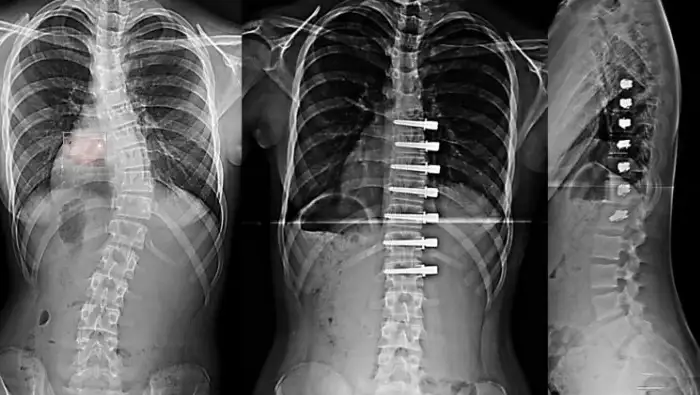

Skolyoz, yani Omurga Eğriliği bulunan hastaların ameliyatla tedavisinde sorunlardan biri, omurganın sabitlenmesi, böylece belirli bölgede omurga hareketliliğinin ortadan kalkmasıdır.

Prof. Dr. Azmi HAMZAOĞLU ve Ekibi’nin uyguladığı GERDİRME YÖNTEMİ (Tethering) sayesinde bu sorun ortadan kalkıyor. Hastanın omurga hareketi yok edilmiyor. Bu durum, özellikle çocuk hastalarda önemli bir avantaj sağlıyor. Çünkü çocuğun büyümesi engellenmemiş oluyor.

GERDİRME YÖNTEMİ ile tedavi edilen çocukların omurgasında, iç bükey yöndeki büyümeye devam ederken, dış bükey yöndeki büyüme vidalara bağlı ip sayesinde duruyor. Böylece zaman içinde eğrilik kendiliğinden düzeliyor. Ameliyat edilen bölge de hareketliliğini koruyor.

GERDİRME YÖNTEMİ sayesinde,

- Omurgada dondurma/sabitleme yapmaya gerek kalmadan eğrilik düzeliyor.

- Hareket kabiliyeti yok olmuyor.

- Çocuklarda büyüme engellenmemiş oluyor.